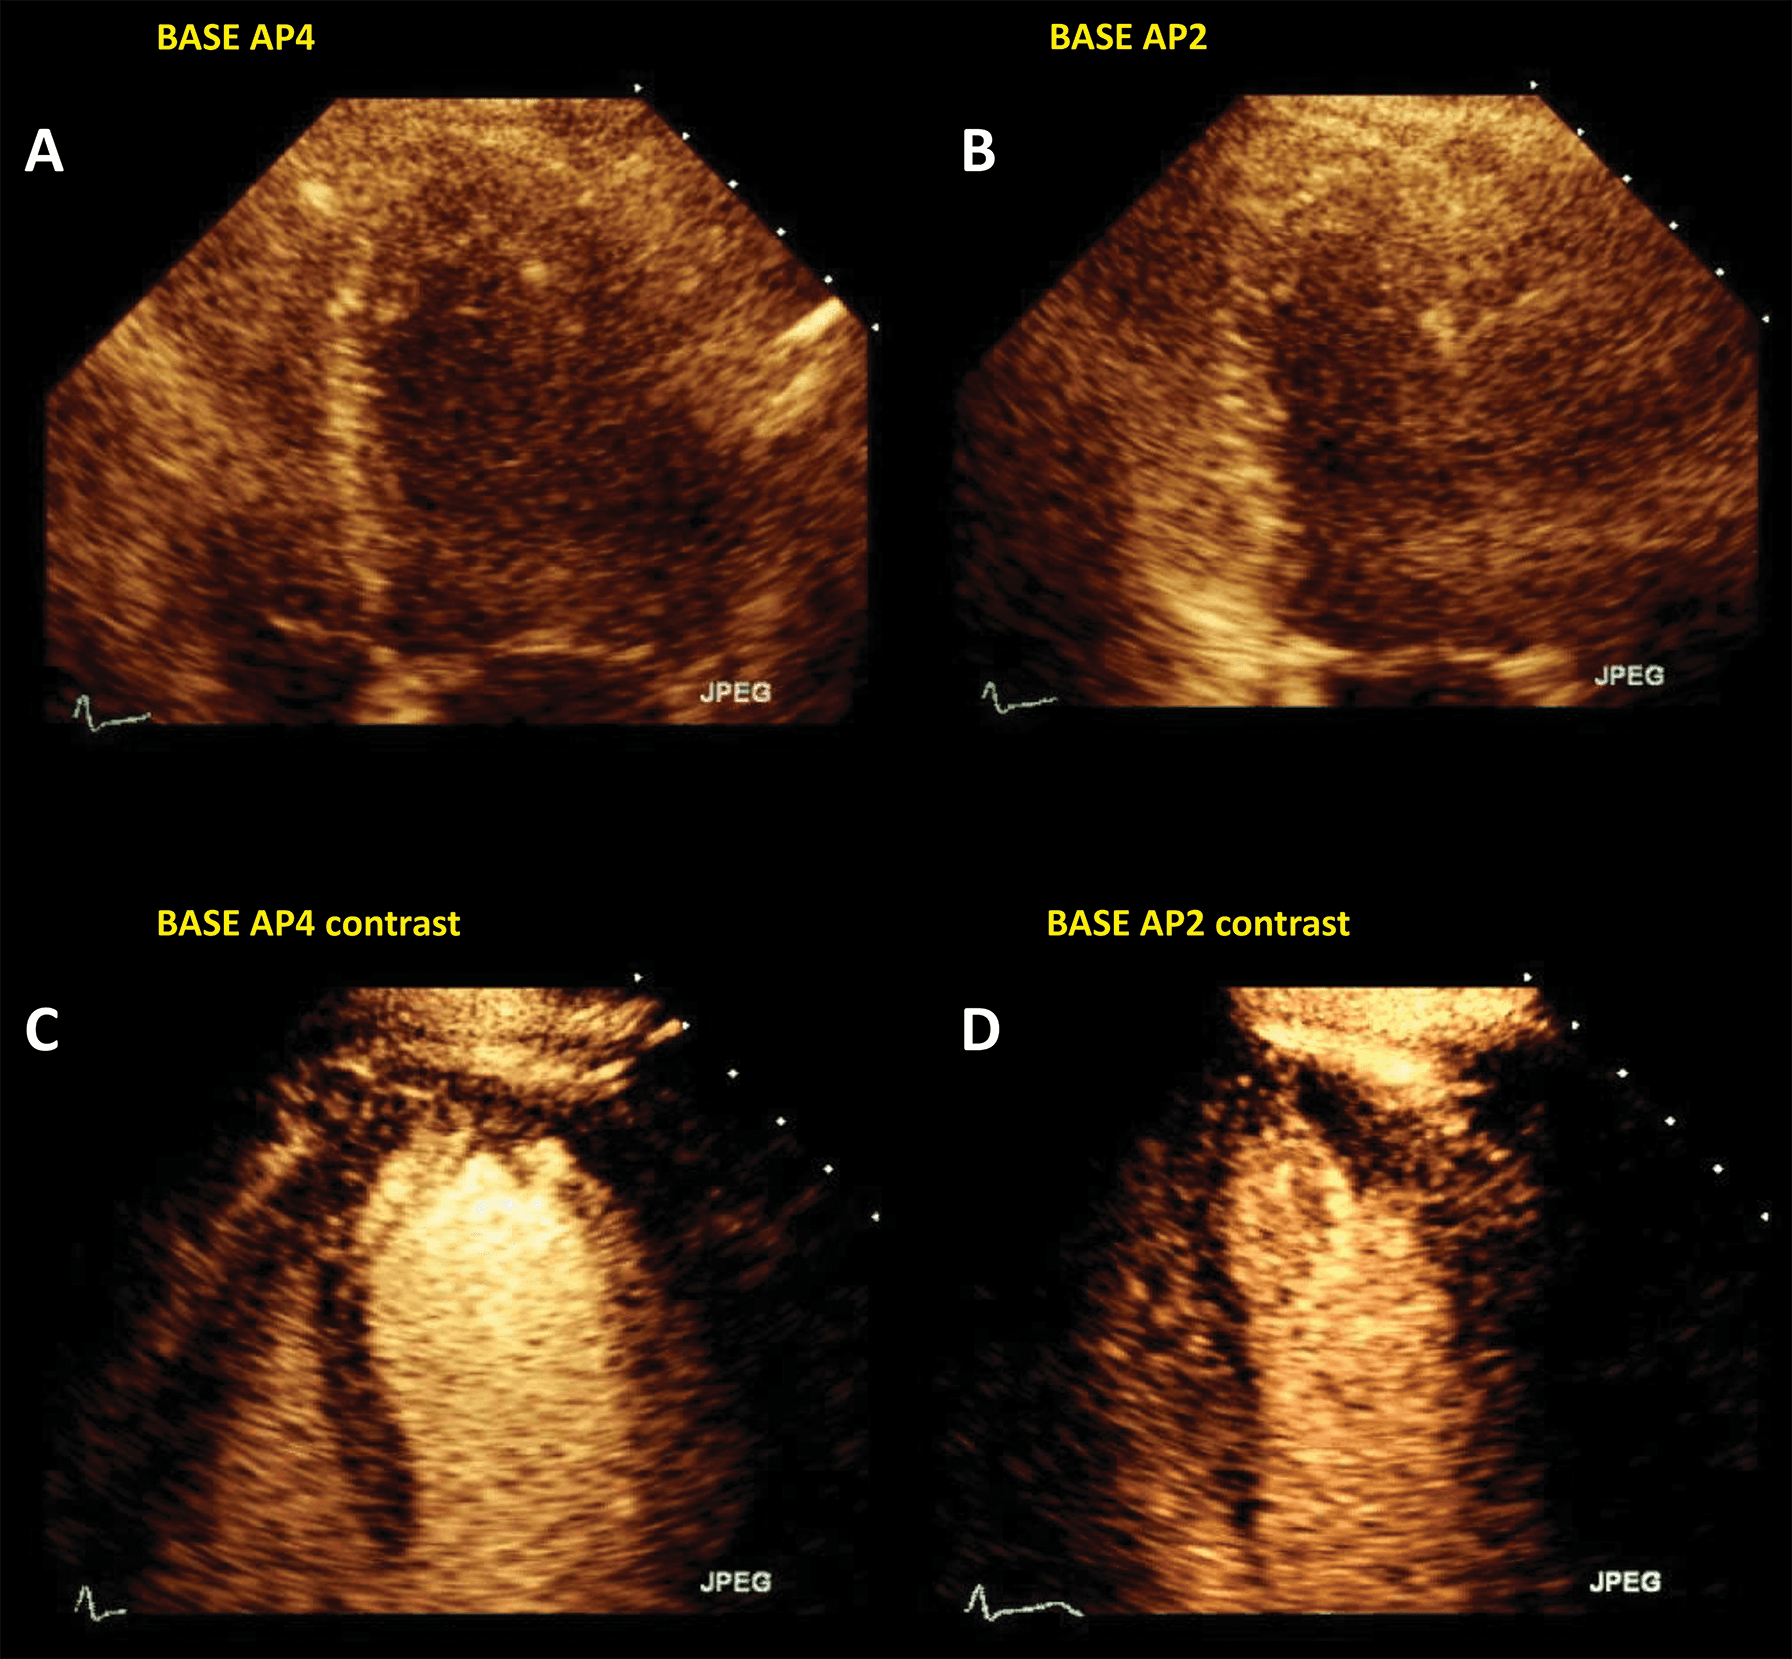

The addition of UEA during stress echocardiography protocols is usually achieved through an LVO application with low-MI harmonic imaging (Fig. 7, Video 6). The result is an increase in the likelihood of a diagnostic test, a better visualization of all myocardial segments, study quality and reader confidence, as compared to invasive or non-invasive reference [40, 41, 42, 43]. The addition of UEA to non-enhanced studies resulted in a better agreement with coronary angiography, even in patients with intermediate coronary lesions [44]. Of course, the use of LVO in stress echo has the largest impact in patients with suboptimal image [45]. Nevertheless, contrast-enhanced ultrasound also improves the wall motion score and detection of regional wall motion abnormalities in patients with adequate image quality [46]. Contrast-enhanced dobutamine stress echocardiography provided adequate risk stratification in patients with increased cardiovascular risk due to obesity or suspected coronary artery disease [47, 48, 49].

Fig. 7.Microbubble enhanced stress echocardiography. Baseline non-enhanced images are recorded in apical 4 and 2 chambers (A,B), demonstrating insufficient delineation of the endocardial borders; With contrast (C,D) the LV contours become clearly visible. Source: personal collection.

In patients with incomplete visualization of at least 2 contiguous segments contrast should be used for stress echocardiography. In patients with adequate image quality, contrast could be used to assess the myocardial perfusion, in addition to wall motion [7, 13].